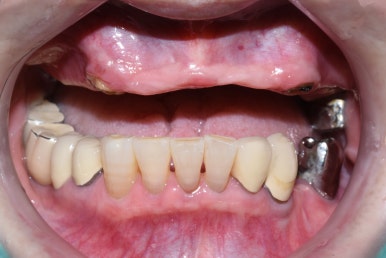

치료 전

어금니부터 일부 앞니까지 연결된 긴 브릿지가 흔들려서 임플란트를 하게 된 케이스

처음 오셨을 때 상태

앞니 뿌리쪽까지 많이 썩어서 삭아 들어가서

앞니 브릿지가 붙을 곳이 없어서 흔들거리고 빠져서 온 상태입니다.

어금니쪽도 다른데서 한 임플란트가 찢어져서 임플란트 머리를 못 올린 상태였고

어금니도 몇 개 상실한 상태입니다.

치료전( 앞니 브릿지 떨어져서 덜렁이는 상태, 다른 곳에서 임플란트 찢어져 실패해서 잇몸에 묻혀진 상태)